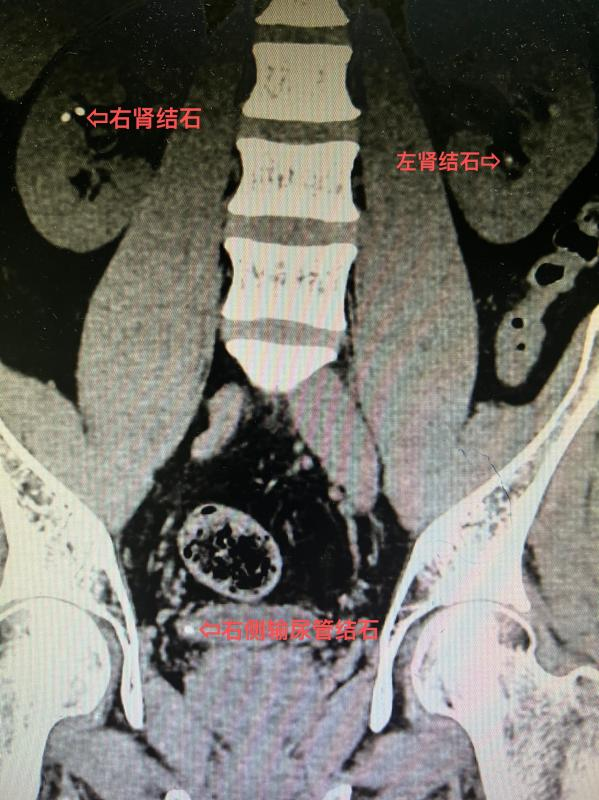

10年前患者检查发现双肾结石,近年来反复出现腰部疼痛,在外院多次行体外冲击波碎石,未见结石排出,症状也没有改善,严重影响了工作和生活。听闻我院泌尿外科在治疗结石方面有丰富的经验,遂慕名前来就诊。泌尿外科拓鹏飞副主任医师接诊后行CT显示:双肾多发结石、右侧输尿管结石。

在患者对自身病情充分知晓并了解诊疗方案后,泌尿外科团队在麻醉手术科团队配合下,为患者顺利实施了同期输尿管软镜下双肾结石钬激光碎石取石术(RIRS)+输尿管硬镜下右侧输尿管结石钬激光碎石取石术(URL),术后复查见结石完全清除,术后第3天患者顺利出院。